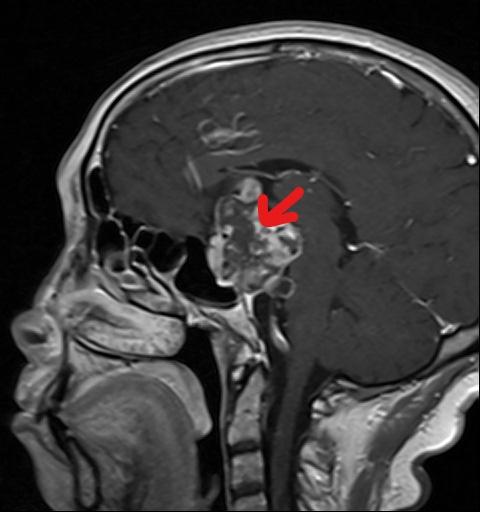

范女士入院后,神经外科全体医师综合讨论了患者病情,并为范女士制定了详细的神经内镜手术方案。完善相关术前准备后,6月25日,科主任任民副主任医师带领神经外科团队为患者在全麻下行"神经内镜经鼻蝶入路垂体瘤切除术+视神经减压术",实现了垂体肿物的内镜下全切,有效解除视神经压迫症状。患者术后3天,自觉视觉功能较术前有明显好转,垂体激素恢复正常,无明显脑脊液漏出现。通过神经外科医护团队的精心治疗和照顾,现已康复出院。

(术后检查显示肿瘤已切除)